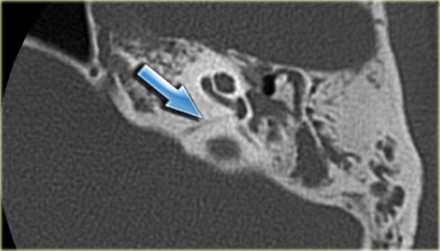

- Внутренний слуховой проход и мостомозжечковый угол - шваннома 8 нерва, менингиома височной кости, эпидермоидные (холестеатомы) и арахноидальные кисты, редко - гломусная тимпаническая опухоль.

Вестибулокохлеарный нерв (VIII) состоит из 4 пучков. Опухоли происходят обычно из вестибулярной его части. Шваннома - инкапсулированная доброкачественная (градация 1) опухоль, происходящая из дифференцированных неопластических шванновских клеток оболочек периферических нервов. Невриномы ММУ составляют около 3% опухолей головного мозга. Часть шванном (двухсторонние слуховых нервов) связана с НФ 2 типа. Пик частоты между 40 и 60 годами. Растут медленно и крайне редко малигнизируются. Клинические проявления связаны с нарушением функции нерва и компрессией ствола. Шваннома может происходить из любого отрезка по ходу нерва и хорошо прослеживается при МРТ области ММУ. Невринома видна как на Т2-взвешенных, так и на Т1-взвешенных МРТ в виде округлого образования. Невриномы хорошо и равномерно усиливаются после МРТ с введением контрастного вещества. Невриномы области цистерны могут иметь компонент во внутреннем слуховом проходе, особенно, хорошо видимый при МРТ головного мозга с контрастированием. Изредка встречаются невриномы полностью расположенные внутри канальца. Они составляют наибольшую диагностическую сложность при МРТ, требуют тонких срезов и контрастирования. Менингиомы ММУ обычно типично расположены и при МРТ имеют характерную форму и типичные черты при МРТ с контрастированием. Однако редко встречаются внутриканальцевые менингиомы. При МРТ они неотличимы от неврином. Холестеатомы при МРТ имеют смешанную интенсивность сигнала, в зависимости от их содержимого. На диффузионно-взвешенных МРТ холестеатомы обычно яркие.

МРТ головного мозга наиболее информативна в плане выявления опухолей мостомозжечкового угла и кист этой области. Некоторое патологии, такие как расширение водопровода и лабиринтит также хорошо видны при МРТ. КТ лучше демонстрирует состояние внутреннего уха.